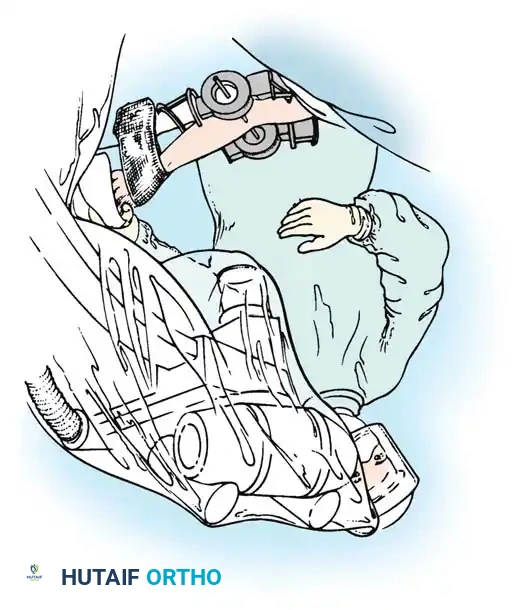

The current gold standard for managing instability following extensive open reduction is the application of a hinged elbow external fixator. Jupiter, Ring, and Hotchkiss have demonstrated excellent results using hinged fixators to maintain concentric joint reduction, permit early active/passive motion, and enhance muscle-tendon stretching.

Fig. 58-25 Late-discovered medial elbow dislocation managed with open reduction and hinged external fixation without primary ligament repair. (From Hotchkiss RN: Fractures and dislocations of the elbow, 1996.)

Hinged External Fixation

Surgical Technique: Compass Hinged Elbow External Fixator (Hotchkiss)

The ulnohumeral articulation is a highly constrained hinge joint. Because only slight movement of the instant center of rotation occurs during flexion and extension, locating the exact rotational axis is the most critical step in applying a dynamic fixator.